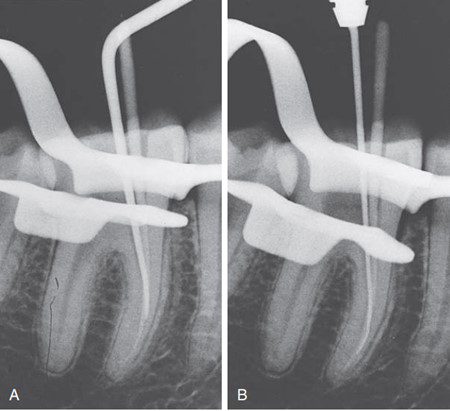

- Chụp X-quang thử côn chính: Hầu hết các bác sĩ chọn chụp X-quang sau khi côn chính được đặt vào ống tủy. Mục đích của “phim X-quang thử côn chính” là kiểm tra xem gutta-percha đã được đặt đúng đến chiều dài làm việc mong muốn hay chưa.

Ngoài ra, bác sĩ có thể chọn thêm một đến hai côn phụ trước khi chụp X-quang. Phim X-quang “lèn ban đầu” này được sử dụng để kiểm tra chiều dài côn gutta-percha chính đảm bảo không bị xê dịch trong quá trình lèn ban đầu, và không có khoảng trống ở 1/3 chóp ống tủy.

Nếu phát hiện lỗi trên phim X-quang côn chính hoặc lèn ban đầu, vẫn có thể dễ dàng rút côn ra khỏi ống tủy trước khi cắt bỏ, và sửa lại hoặc chọn côn chính mới. Rút côn ra khỏi ống tủy một cách chậm rãi.